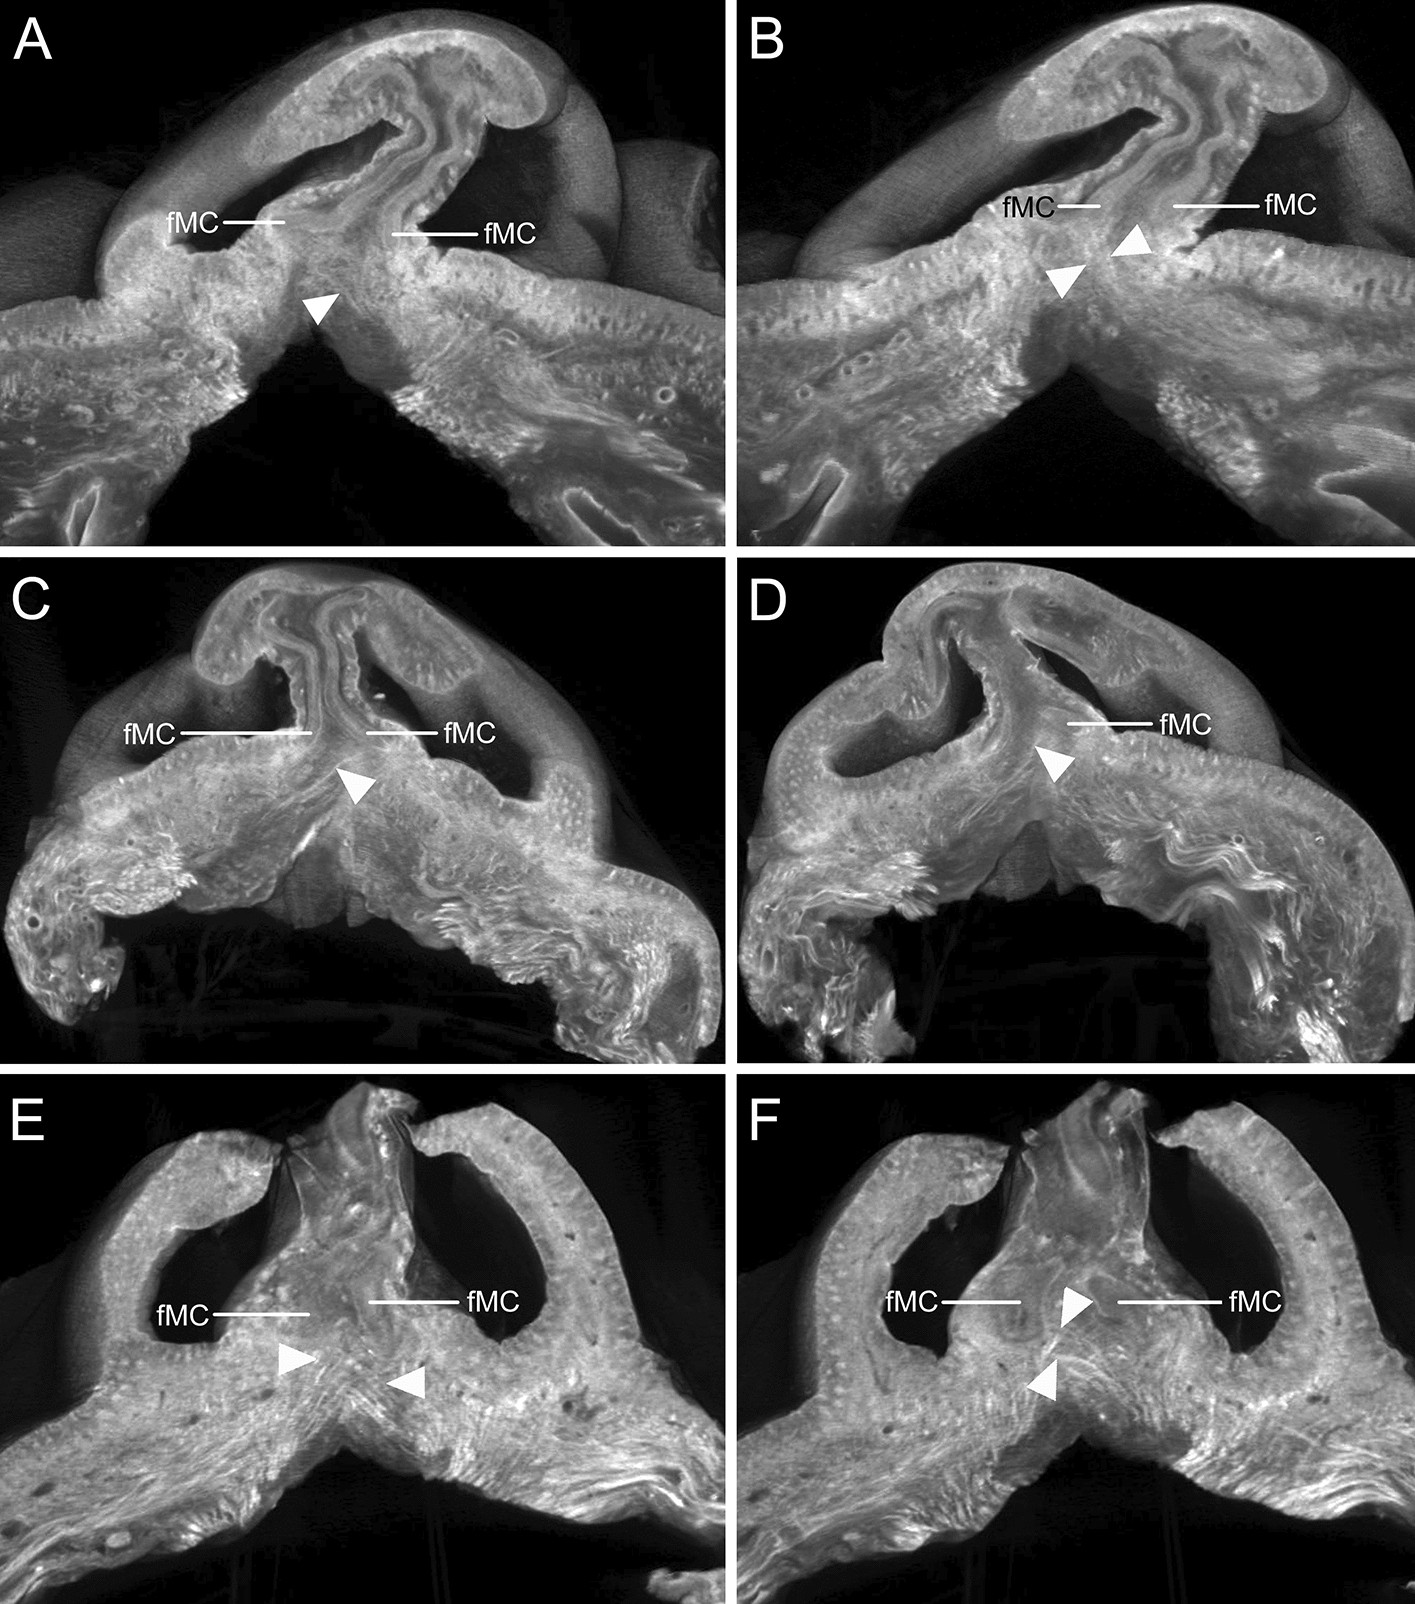

Figure 3

Micro-CT images of the crossing fibers of the DSN (arrowheads) in the plane parallel to the nostrils. (A and B) Some crossing fibers of the left DSN appeared to attach to the fMC on the right side. (C and D) Some crossing fibers of the right DSN appeared to attach to the fMC on the left side. Serial images of the crossing fibers of the DSN in the plane parallel to the nostrils are presented in the supplementary videos. (E) Crossing fibers of both the DSNs appeared to attach to the fMCs on the contralateral sides. (F) At deeper sites, some crossing fibers of the left DSN appeared to attach to the fMC on the right side. Serial images of the crossing fibers of the DSN are presented in Supplementary Videos S2–S4.